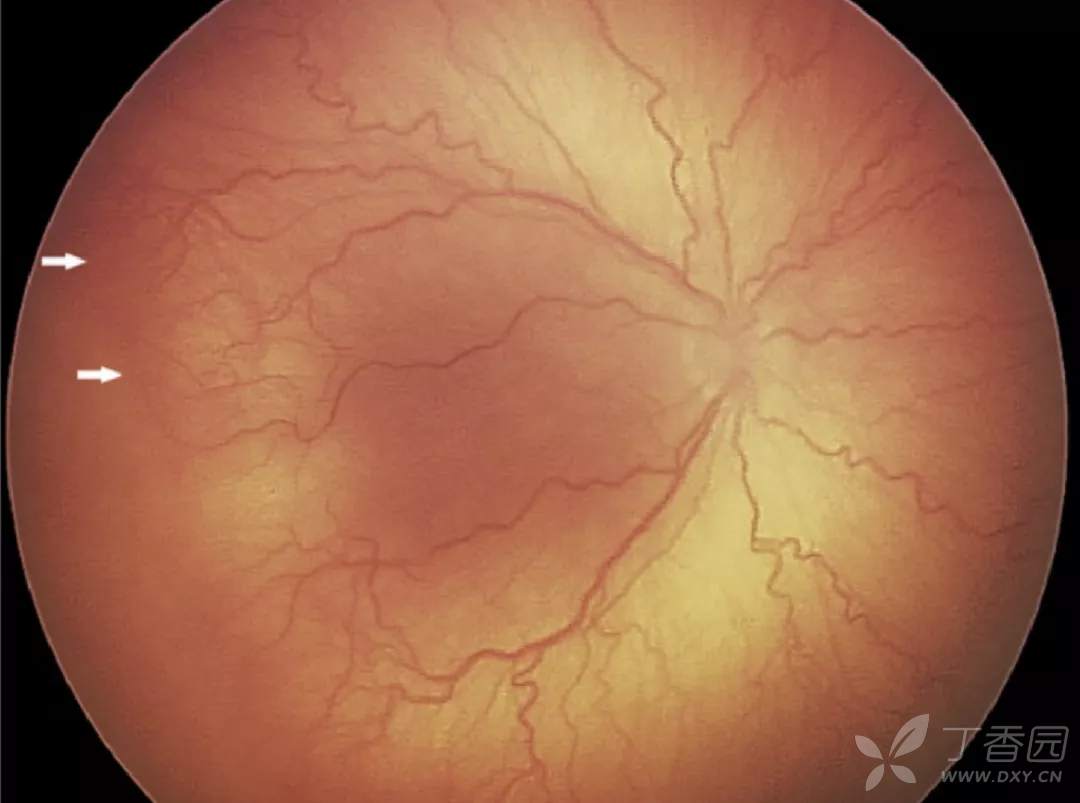

02、plus病变和plus病变前期

plus病变指视网膜血管扩张和迂曲。plus病变前期定义为视网膜血管异常扩张和迂曲,但不足以诊断为plus病变。

图. 严重plus病变,动、静脉纡曲扩张。

图. 严重plus病变,伴后极部3期病变(箭头),是典型的急进型ROP。